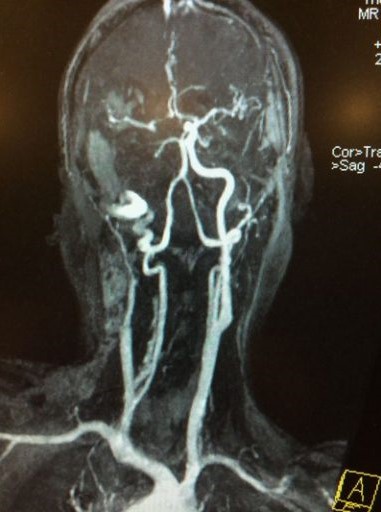

羅先生被送往私家醫院的第一步是進行緊急磁力共振造影,報告顯示羅先生右邊頸和腦部血管大動脈全部都被血栓堵塞着,右邊大腦缺血水腫,導致左邊手腳冇力和神智半昏迷。經過腦血管外科醫生的診斷和急救,在全身麻醉下,醫生使用尤如髪絲微細的導管,經過病人右邊大腿的腹股溝的大動脈而入,導管再經過腹部和胸腔的大動脈一直向上,遊走到病人右邊的頸和腦部血管大動脈,進行機械式血栓吸取內血管治療急救。